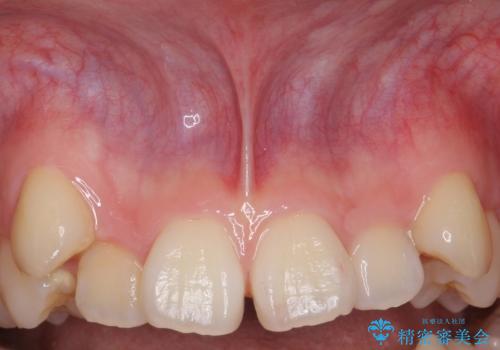

- 上顎前歯の隙間と出っ歯、八重歯が気になるため矯正をしたいといらっしゃった方の症例です。

上顎前歯の隙間と出っ歯の一因は上唇小帯と呼ばれる上唇と歯茎を結ぶ線維性の付着によるものであり、矯正を行っても後戻りのリスクが高いことから、矯正前に上唇小帯の切除を行いました。

上唇小帯とは上唇と歯茎を結ぶ線維性の付着のことです。上唇小帯の付着位置が前歯に近いと今回のケースのように正中離開(前歯の隙間)の原因となります。